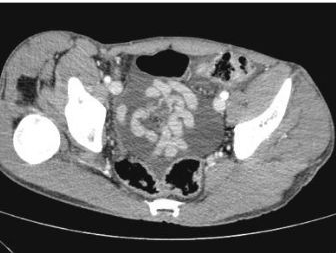

Paciente pós trauma contuso (fechado) estável com hematúria e imagem abaixo * Conduta?

* Trata-se de um hematoma subcapsular renal, ou seja lesão de viscera sólida * Todavia, mesmo com isso, estando o paciente estável, a conduta é sempre conservadora com vigilância criteriosa * Caso haja piora persistente, pode se fazer arteriografia com embolização se blush na fase aguda do trauma ou sangramento tardio * Se paciente instável, provavelmente vai apresentar **hematoma pulsátil ou em expansão**, logo, fazer cirurgia

TC ABDOMINAL E PELVICO TRIFÁSICO * Fases * O que é avaliado em cada uma delas

Sempre soliticar após trauma abdominal **1 fase (sem contraste)** * Avaliar se há sangramento ativo * O sangue é hiperatenuante (branco) (presente na imagem) **2 fase (arterial)** * Aorta e outras artérias ficam brancas * Verificar se não há extravazamento de sangue! (não está presente na imagem acima) * Cortex fica branco, mas a medula continua cinza **3 fase (portal)** * Rim e veias inteiramente contrastadas (brancas) * Se alguma área estiver preta, indica lesão vascular **4 fase (extretora)** * Contraste nos calices * Verificar se há extravasamento de contraste